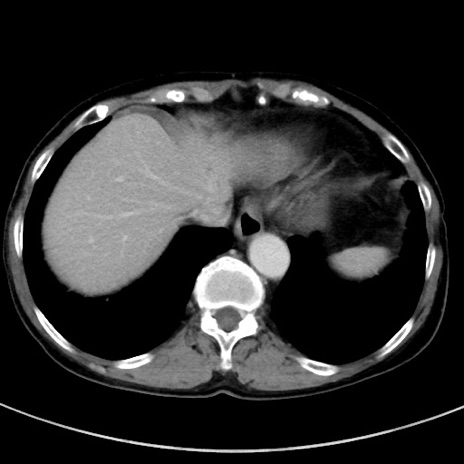

冠状断像

【症例】70歳代女性

【主訴】下腹部痛・嘔吐

【現病歴】2日前より腹痛あり。昨日嘔吐あり。症状改善しないため来院。

【既往歴】胃GISTに対して胃部分切除後。

【身体所見】BT 37.1℃、BP 128/77mmHg、腹部:平坦・軟、下腹部に圧痛あり。

【データ】WBC 10200、CRP 0.31